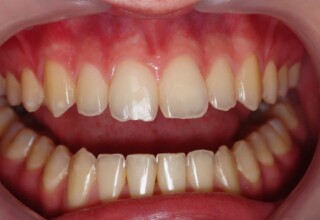

Τα απονευρωμένα δόντια πολλές φορές χάνουν την φωτεινότητα τους και σκουραίνουν σε αντιαισθητικό επίπεδο. Η λεύκανση τους προϋποθέτει άψογη απονεύρωση και υπομονή. Τοποθετείται ένα σφράγισμα στη ρίζα του δοντιού για να περιοριστεί η δράση του λευκαντικού υγρού μόνο στο τμήμα του δοντιού που είναι εμφανές στην στοματική κοιλότητα. Στην συνεχεία απαιτούνται 1-5 σύντομες συνεδρίες τοποθέτησης του λευκαντικού υλικού. Μετά τον αποχρωματισμό του δοντιού τοποθετείται ένα σφράγισμα ρητίνης με άψογη συγκόλληση για όσο το δυνατόν μακροχρόνια αποφυγή της μικροδιείσδυσης.

Αρχική εμφάνιση

Τελική εμφάνιση